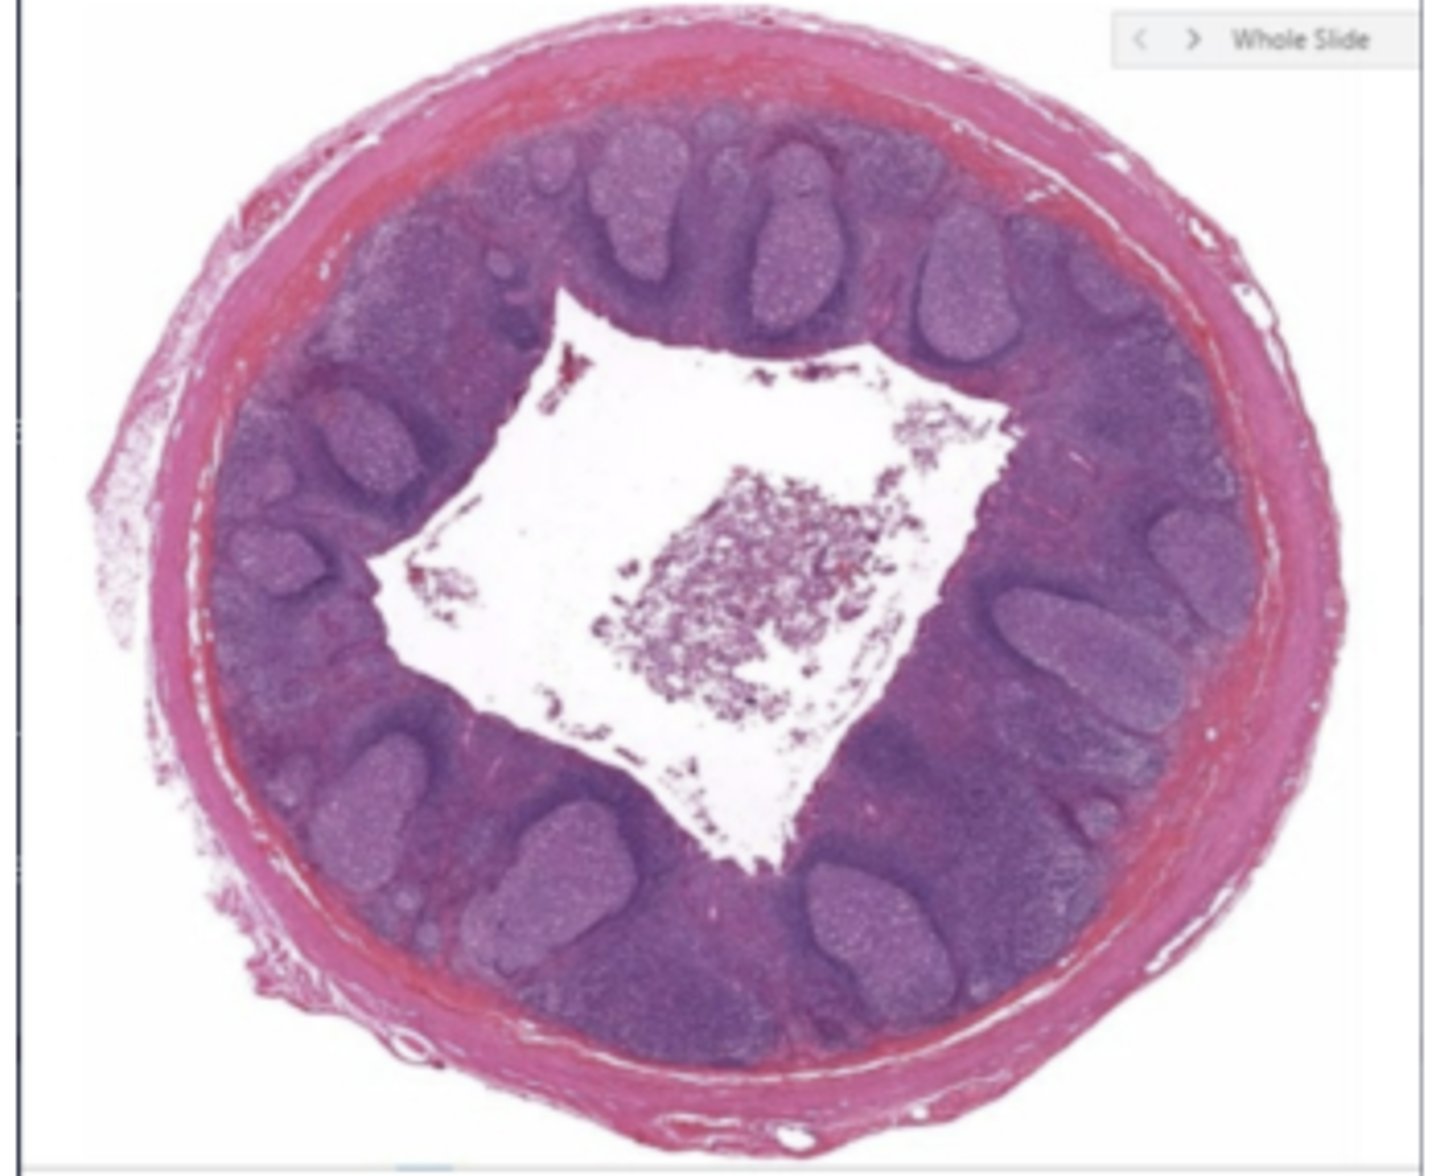

seminiferous tubules

epididymis

spermatozoa

seminal vesicle